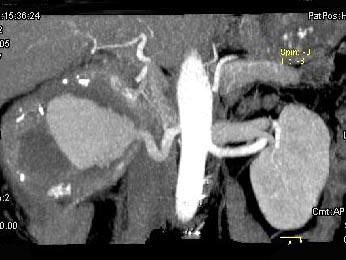

问题 男,48岁,反复腰酸、腰痛伴镜下血尿2年,加重3天,无尿频、尿急、尿痛,无低热、盗汗、咳嗽,右肾区叩击痛,CT检查如图所示,应诊断为 ( )

选项 A、右肾错构瘤 B、右肾盂癌 C、右肾癌 D、急性右肾内血肿 E、右肾动脉瘤

答案 E